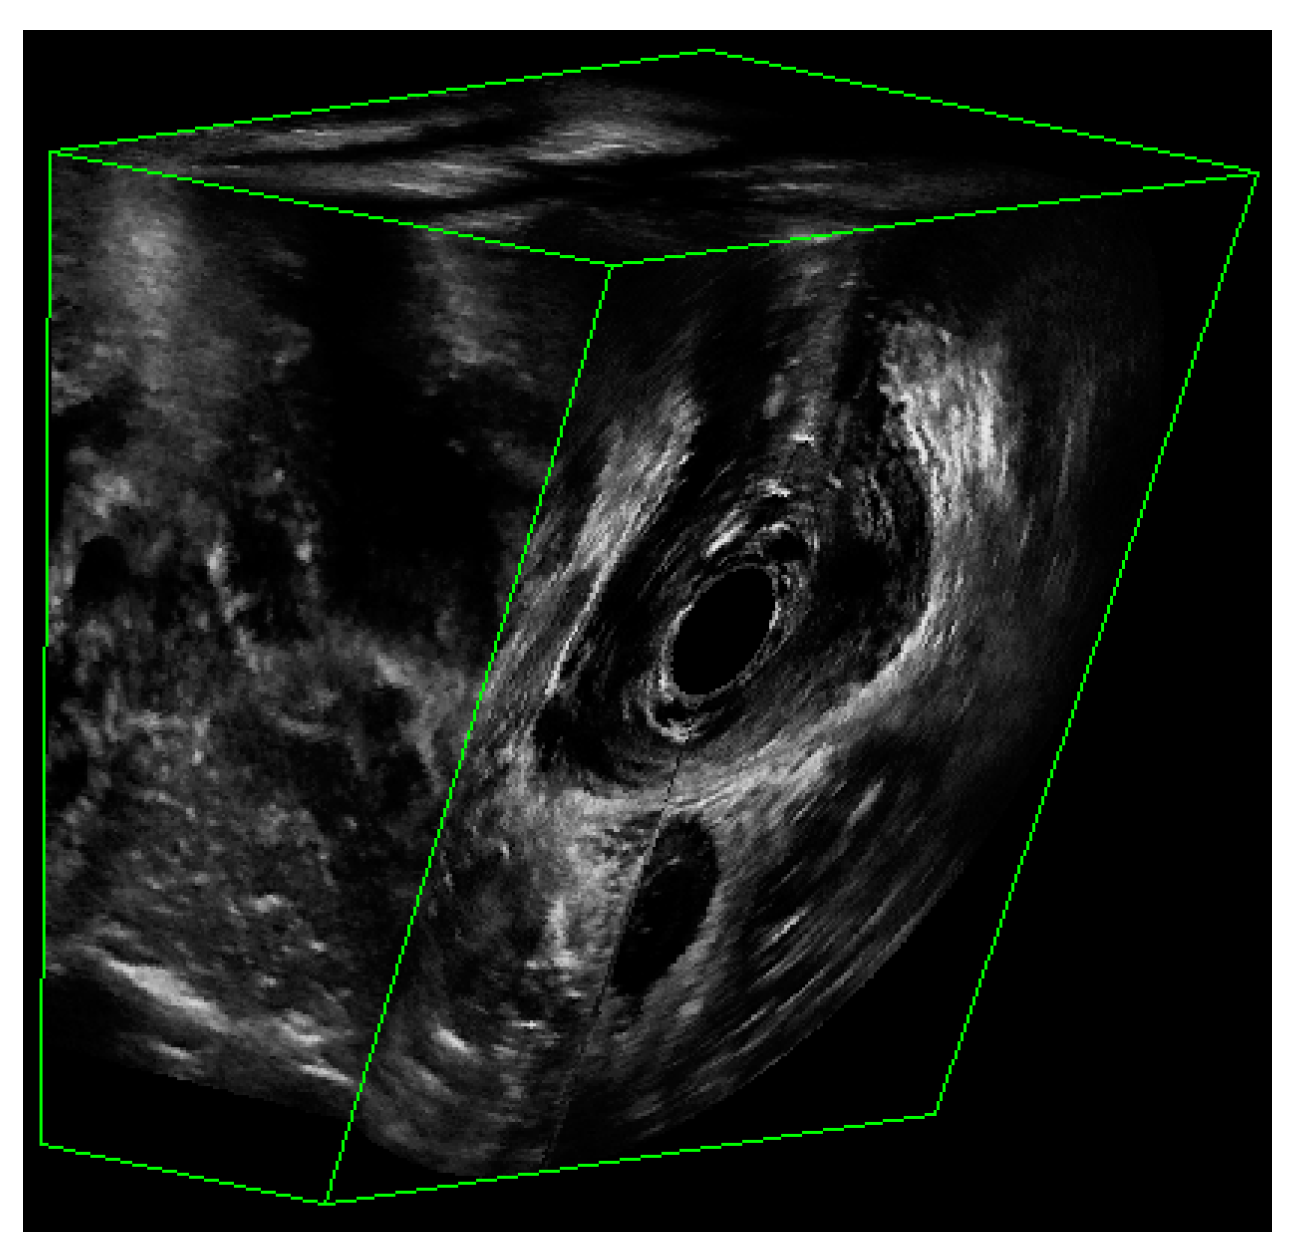

- Asif, Z.; Tomashev, R.; Peterkin, V.; Wei, Q.; Alshiek, J.; Yael, B.; Shobeiri, S.A. Levator ani muscle volume and architecture in normal vs. muscle damage patients using 3D endovaginal ultrasound: A pilot study. Int. Urogynecol. J. 2022. [Google Scholar] [CrossRef] [PubMed]